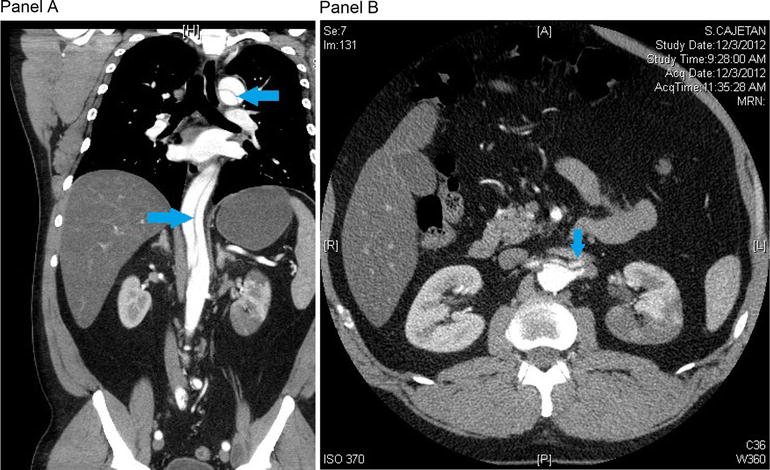

Follow-up CT scan. CT scan obtained three and a half months after discharge demonstrated a Stanford type B aortic dissection with the intimal flap originating just distal to the origin of the left subclavian artery and extending to the descending portion of the thoracic aorta (Panel A, 3D reconstruction, blue arrow). There was no involvement of the great vessels. A marked perfusion defect in the upper pole of the left kidney with associated interval atrophy of the left upper pole was seen (Panel B, blue arrow). Unchanged aneurysmal dilatation of the proximal abdominal aorta, measuring 3.3 × 3.3 cm, was present